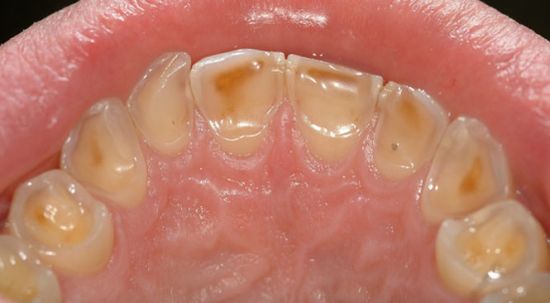

在牙侵蚀症的早期阶段,牙釉质表层会被侵蚀掉,而在后期阶段,就会使得较柔软的牙质甚至牙齿中央柔软的部分(牙髓)裸露出来。

(在牙侵蚀症的)早期阶段,牙侵蚀症会造成牙齿对冷食物敏感。如果发展下去,接下来可能会造成更严重的疼痛。并不是所有的无糖口香糖都包含食品酸味剂,通常来讲,相比其他口味的口香糖,薄荷味口香糖造成侵蚀的可能性要小些。

(牙侵蚀症)早期阶段

牙侵蚀症—由于酸侵蚀对牙齿造成的不可逆损伤。